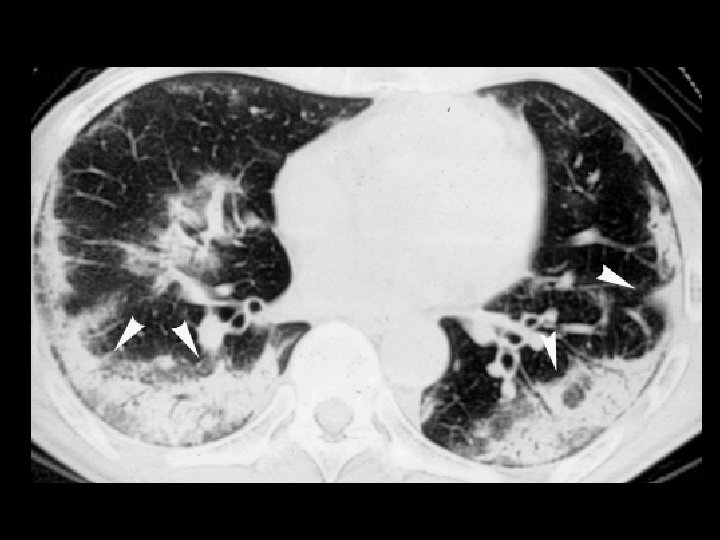

Cystic fibrosis • Findings: – Diffuse bronchiectasis – hyperinflation – mild enlargement of central pulmonary arteries • ddx: – Immotile ciliary syndrome – immunodeficinecy & chronic infections

Tuberculosis • Findings: – patchy parenchymal opacities – focal bronchiectasis and accompanying bronchioliltis – bilateral distribution • ddx: – endobronchial spread of tumor